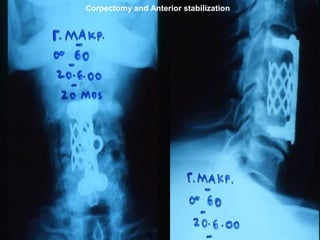

Corpectomies and Anterior stabilization

Corpectomy and Anterior stabilization